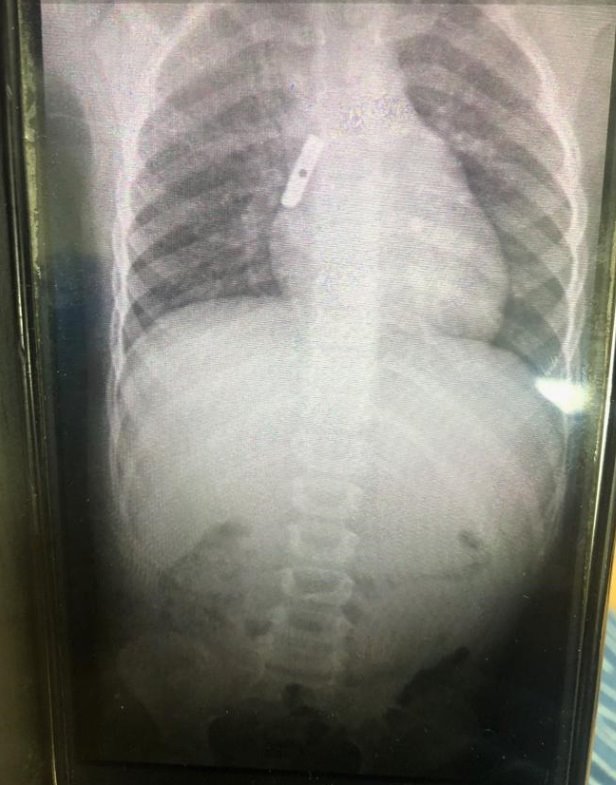

בהדמיה שבוצעה לילדה הודגם להב המחדד בסימפון הריאה הימנית ולאחר התייעצות של ד"ר גריגורי זלוטין , ד"ר תום ברנשטטר, רופאי אף אוזן וגרון וד"ר סרגי צרגורודצב, מומחה בהרדמה, עם פרופ' אביב גולדברט, מנהל מחלקת ילדים ב' ומומחה ברפואת ריאות בילדים, הוכנסה הילדה בדחיפות לניתוח בהרדמה כללית, בה שלפו הרופאים את להב המחדד מסימפון הריאה הימנית דרך קנה הנשימה בפעולת באמצעות ברונכוסקופיה גמישה.

ד"ר תום ברנשטטר, רופא במחלקה לאף אוזן וגרון בסורוקה הוסיף: "אחד הסימנים לגוף זר אצל ילדים הוא קושי בבליעה שמלווה בריור או בשיעול טורדני. בצילום שבוצע, ניתן היה לראות כי הילדה אכן בלעה להב שחדר לריאה. בכל ימות השנה ובפתיחת שנת הלימודים בפרט מומלץ לשים לב שכן ילדים מכניסים חפצים לפה, דבר שעשוי להיות מסוכן עד כדי סכנת חיים".